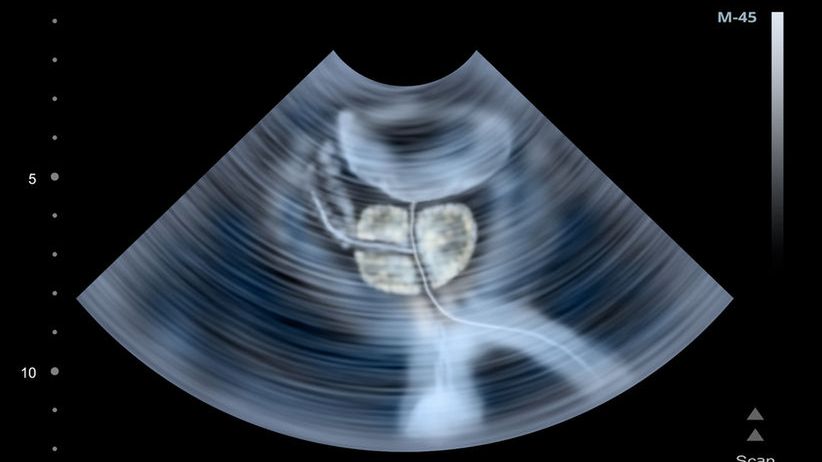

Rak prostaty to jeden z najczęstszych nowotworów u mężczyznRak prostaty to jeden z najczęstszych nowotworów u mężczyzn

Źródło zdjęć: © 9123rf) Rak prostaty to jeden z najczęstszych nowotworów u mężczyzn